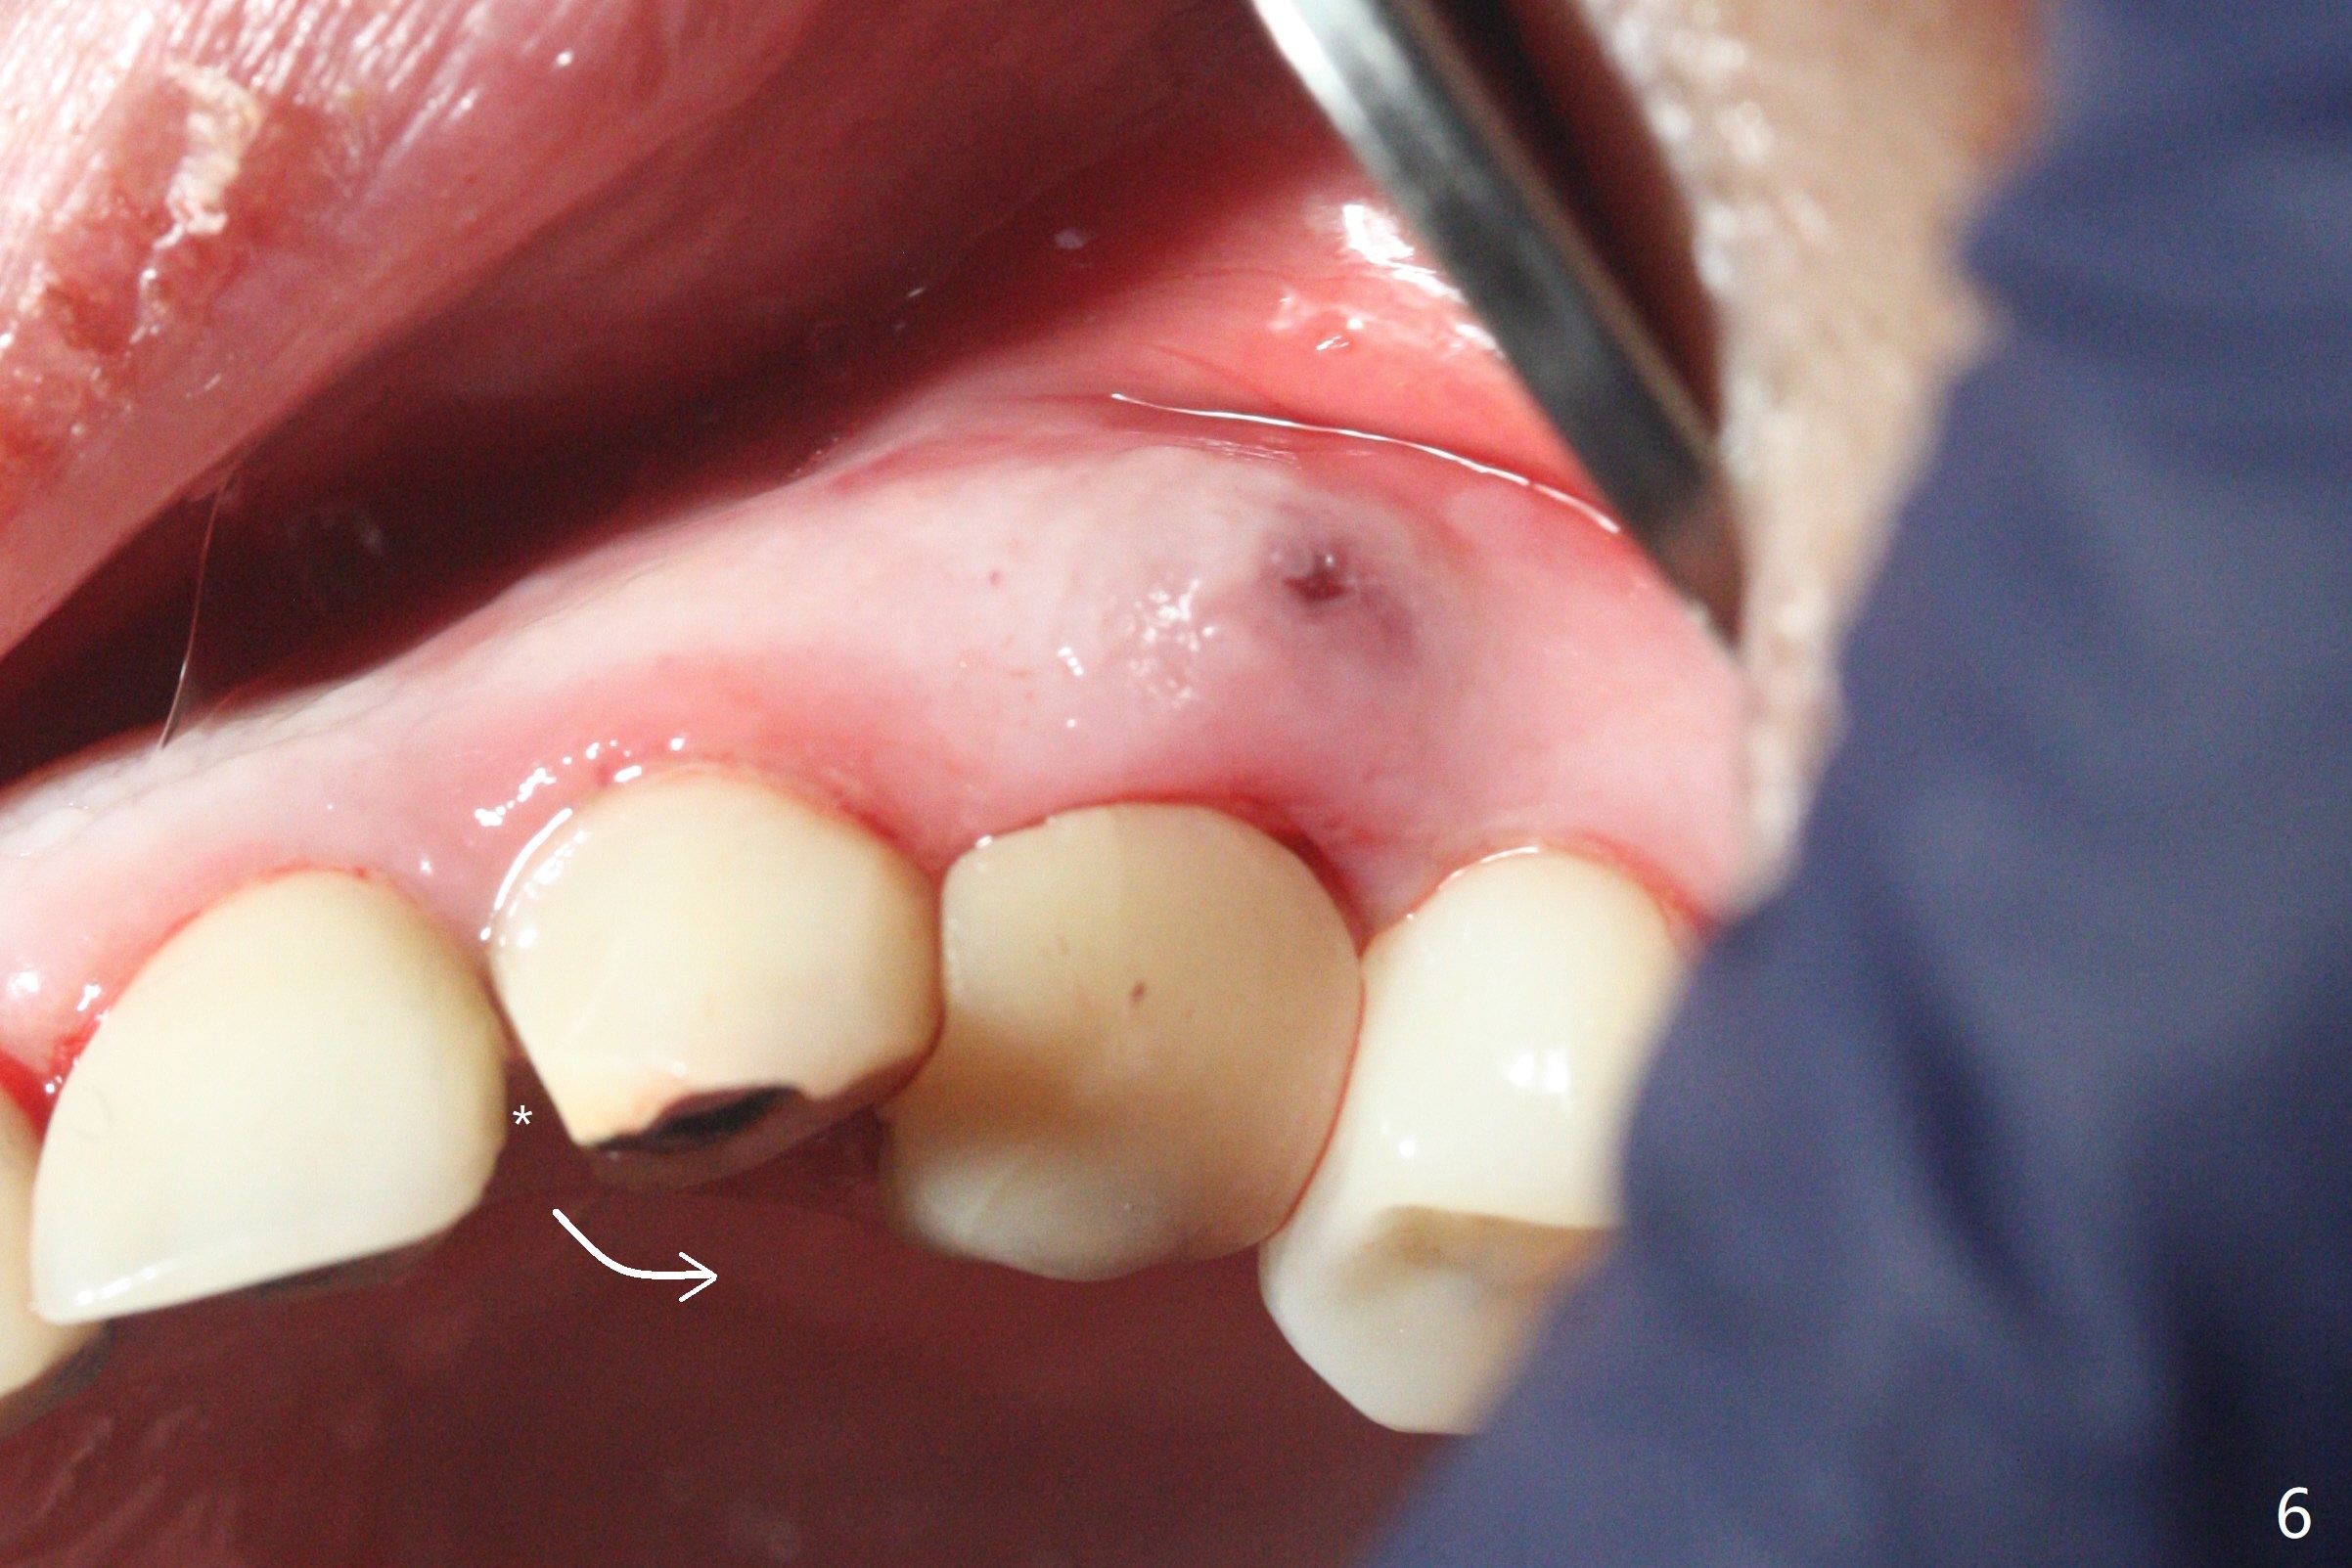

52岁女左上4颊侧牙龈显著肿胀(图一:*(颊侧骨板缺失))伴有瘘道(<),拔除前,在3植牙牙冠切缘舌侧形成开口(图二:*,准备纠正基台不全就位(<);4初步钻洞不正。改变钻头方向后(图三),完成植体放置(图四),并且安置修复基台(4.5x4(2))。磨去3牙冠近中面(图六:*),牙冠和基台反时针旋转(图六:弯箭头),基台完全就位(图四:箭头),调𬌗后,制作4临时牙冠(图六),放置后者前,覆盖半张PRF膜(促进下面粘性骨粉愈合)。图五,六颊侧隆起是因为下面放置许多粘性骨粉。图七是术前CT3D图像(冠状切面),显示颊侧(B),腭侧(P)牙根。拔牙后显示中隔(图八:S),植体植入腭侧窝(图九:绿色),四面骨质包绕,包括中隔;为了修复颊侧骨板,首先放置半张PRF膜(红色)紧贴颊侧骨板腭侧/牙龈,防止骨粉从瘘道流失,然后放置粘性骨粉(图十:粉红色)。术后2.5月3颊侧牙龈仍然红肿(图十一,十二:*),可能与基台袖太短有关(2毫米,图二至四),所以更换袖3毫米的基台(图十三)。术后四个月(牙冠粘固)3颊侧牙龈炎症明显减退(资料没有显示)。术后2.5月4颊侧骨板没有塌陷(图十二,与术后即刻对比(图六))。3基台放置太颊侧,所以在牙冠腭侧制作小的开口(图十四:>),让多余粘固剂流出。取模前3螺丝就拧紧(35Ncm),而4由于有大的开口,粘固后才拧紧(30Ncm)。两个邻牙其中一个可以取出,容易去除另外一个牙冠残余粘固剂。